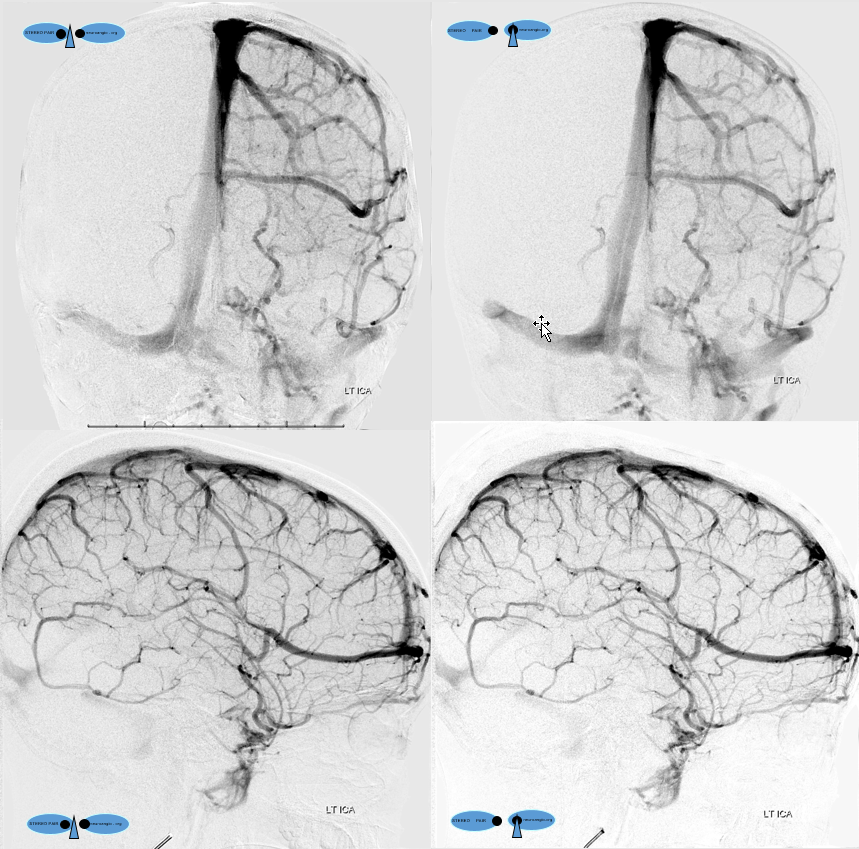

Following embolization, resection, recurrence (as frequently the case with childhood AVMs) and gamma-knife, things look good. Stereo, of course.

Following embolization, resection, recurrence (as frequently the case with childhood AVMs) and gamma-knife, things look good. Stereo, of course.